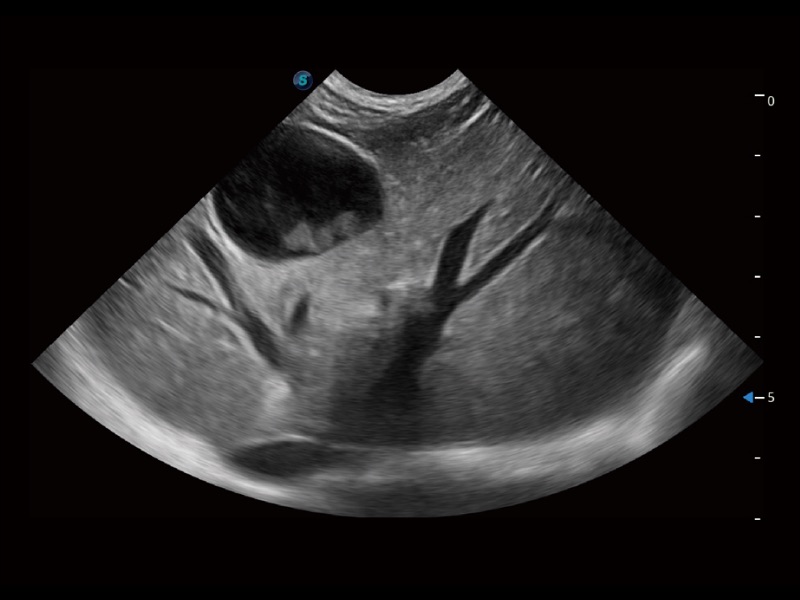

动物是人类最亲密的朋友和最值得信赖的伙伴。玖鼎集团也一直致力于探索动物专用的超声影像解决方案。全新推出的ProPet系列,是玖鼎集团在动物超声影像智能化、专业化、精准化的一次跨越式革新。动物不能用言语来表述自己的不适,通过超声影像,ProPet系列搭建了动物医生与不同物种沟通的“桥梁”,为动物医生注入了“治愈之力”。 ProPet 70将是您值得信赖的超声伙伴。它配备了复合材料线阵探头,帮助动物医生获得卓越精准的临床图像。同时ProPet 70直观便捷的操作体验以及专业的测量工具,可为不同体型和生理结构的动物带来全面临床评估,切实为动物医生提供智能、专业、精准的超声影像解决方案。

ProPet 70 进一步提升了微米成像算法,更加注重对基础原始图像的还原和保留,在有效减少斑点噪声、增强组织边界显示的同时,避免过度优化丟失真实的解剖信息。

ProPet 70专为动物医生设计,对不同的动物体型和生理结构作出了针对性的优化。通过动物影像专用软件,可满足个性化的应用需求,帮助动物医生获得更精确的诊断数据。

ProPet 70 全新的动物超声智能软件和丰富的探头群,为动物医生提供了高清晰度和精细分辨率的图像,无论在宠物、马科、畜牧还是实验室动物等应用中都可以轻松应对,为您的日常工作带来满意的体验。